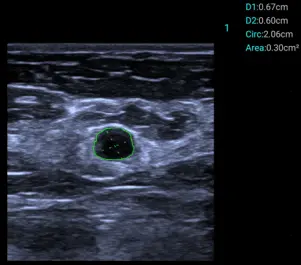

Smart Calc

Полуавтоматично измерване на диаметър и площ на лезии.

Клинични снимки